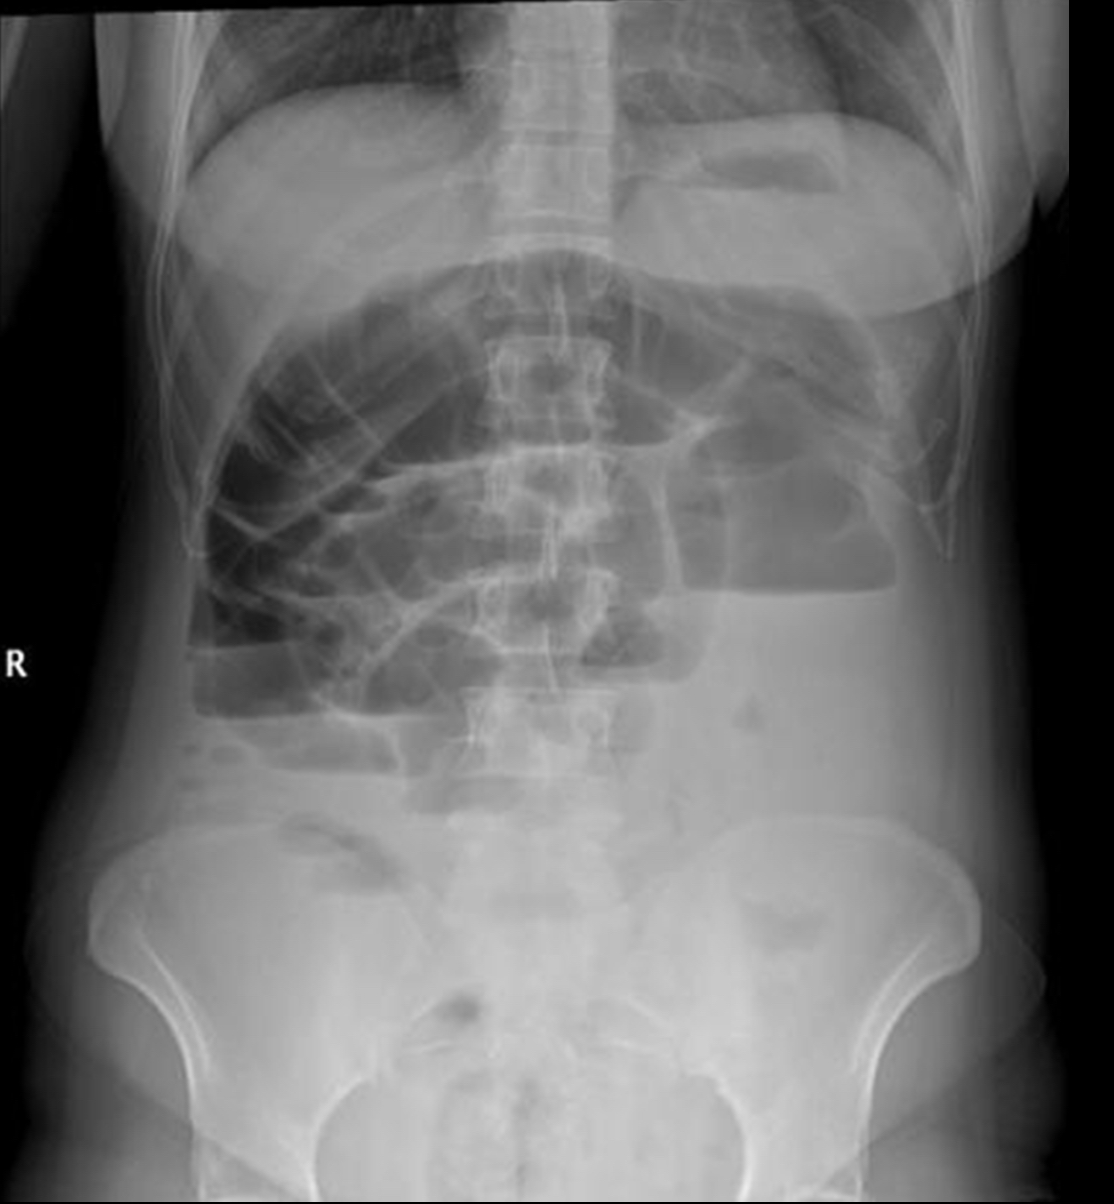

bowel obstruction

partial or full blockage of large or small bowel that does not allow substances to pass through

radiographic appearance of bowel obstruction

dilation of bowel

technical factors of bowel obstruction

depending on blockage, may need to increase/decrease

What pathology is this?